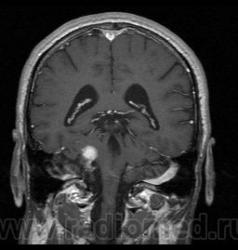

Пациент 35 лет, направлен неврологом из поликлиники с Ds: Рассеянный склероз? У данного пациента в течении года отмечается сильное головокружение и шаткость в походке, пришел на исследование на плечах у родственников. Данное исследование закачено на Dicom-сервер http: //www.radiomed.ru:8080/oviyam/oviyam? (под названием Brain-20101118).

Невринома правого слухового нерва

Если быть точным, VIII нерва;)

Более вероятнее невринома правого слухового нерва.